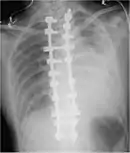

Chest X-ray

Two chest X-rays: left showing a massive left-sided hemothorax; right showing a massive right hemothorax

A chest X-ray is the most common technique used to diagnosis a hemothorax.[23] X-rays should ideally be taken in an upright position (an erect chest X-ray), but may be performed with the person lying on their back (supine) if an erect chest X-ray is not feasible. On an erect chest X-ray, a hemothorax is suggested by blunting of the costophrenic angle or partial or complete opacification of the affected half of the thorax. On a supine film the blood tends to layer in the pleural space, but can be appreciated as a haziness of one half of the thorax relative to the other.[5] A small hemothorax may be missed on a chest X-ray as several hundred milliliters of blood can be hidden by the diaphragm and abdominal viscera on an erect film. Supine X-rays are even less sensitive and as much as one liter of blood can be missed on a supine film.[24]